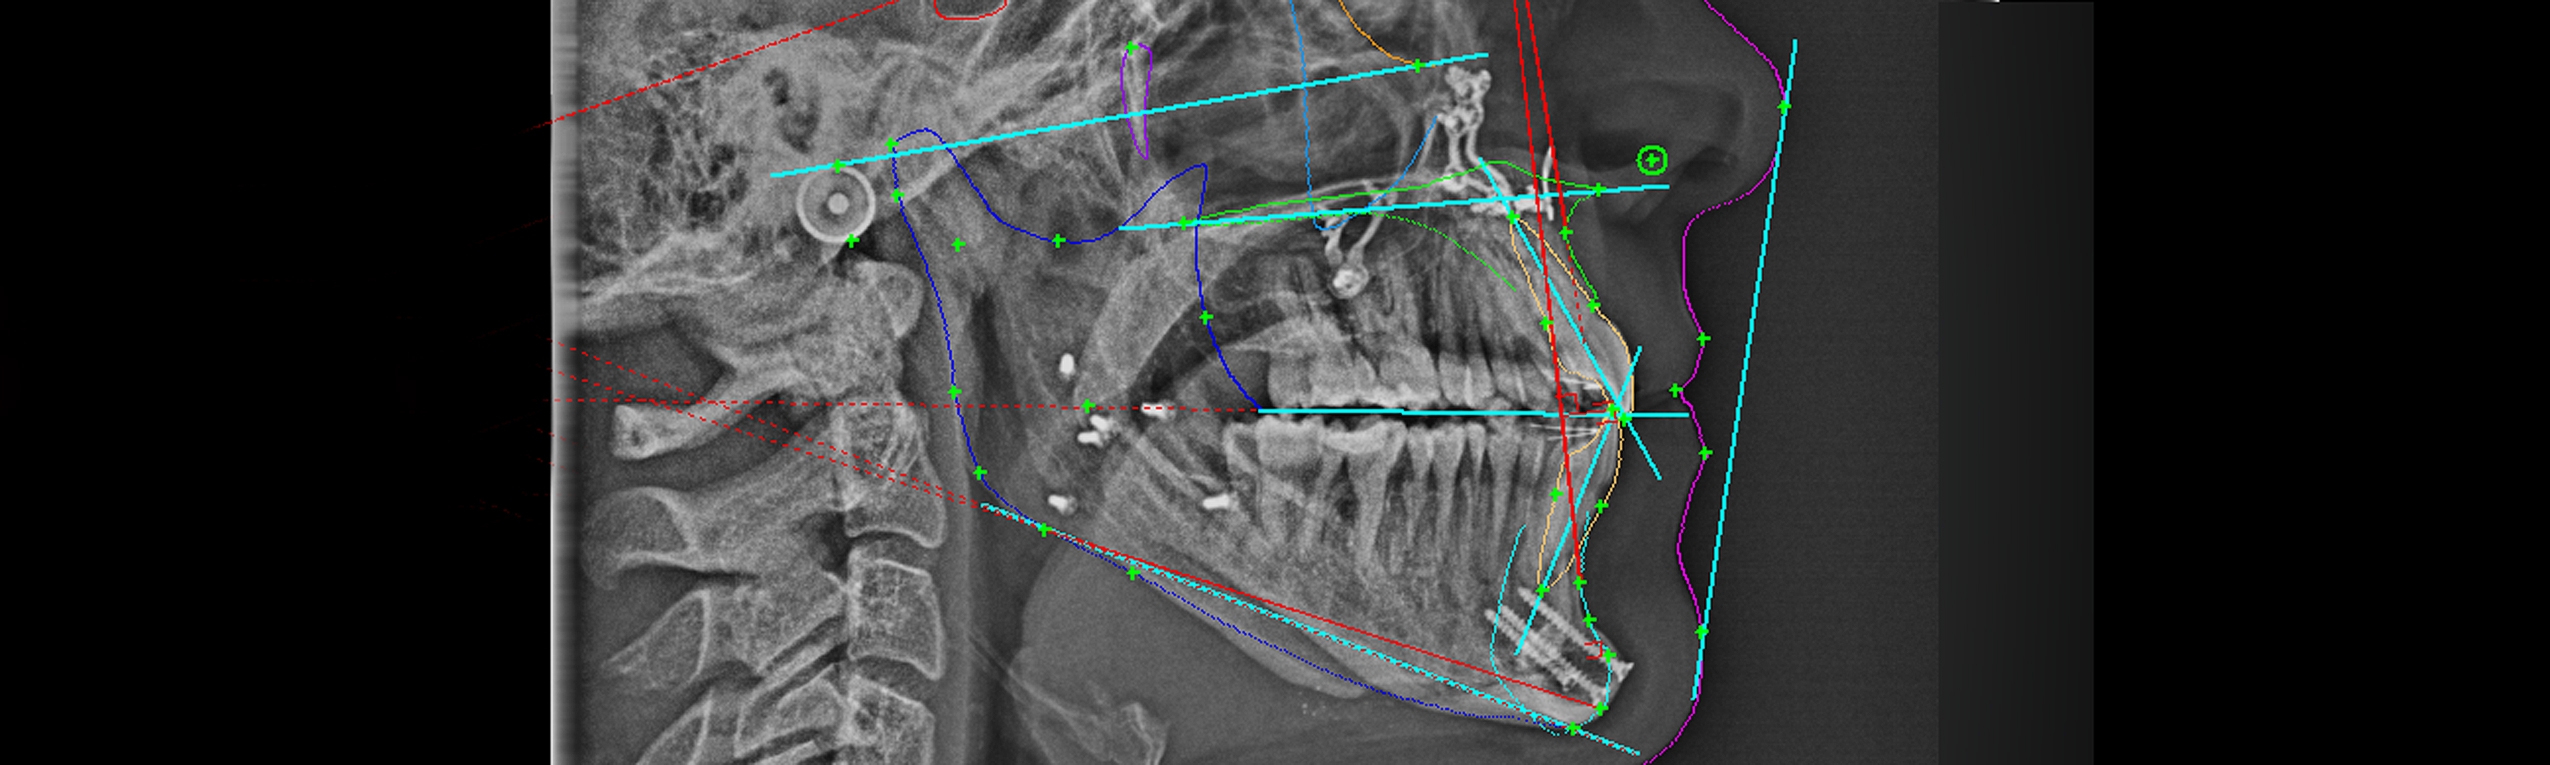

A correção cirúrgica (cirurgia ortognática) pode ser necessária em casos de pacientes adultos com discrepâncias esqueléticas (ou seja, questões relacionadas com o tamanho, posição ou forma dos maxilares). Nestas situações, há tratamento combinado entre ortodontia e cirurgia ortognática. O tratamento começa com aparelhos ortodonticos até os dentes estarem bem posicionados em relação ao seu respetivo maxilar. Com este objectivo alcançado, o cirurgião especializado em cirurgia ortognática, corrigirá cirurgicamente a posição dos maxilares.

Esse tipo de tratamento requer uma ótima coordenação entre o ortodontista e o cirurgião. Só o bom trabalho em equipe permite excelentes resultados, mesmo em situações mais complexas e difíceis.